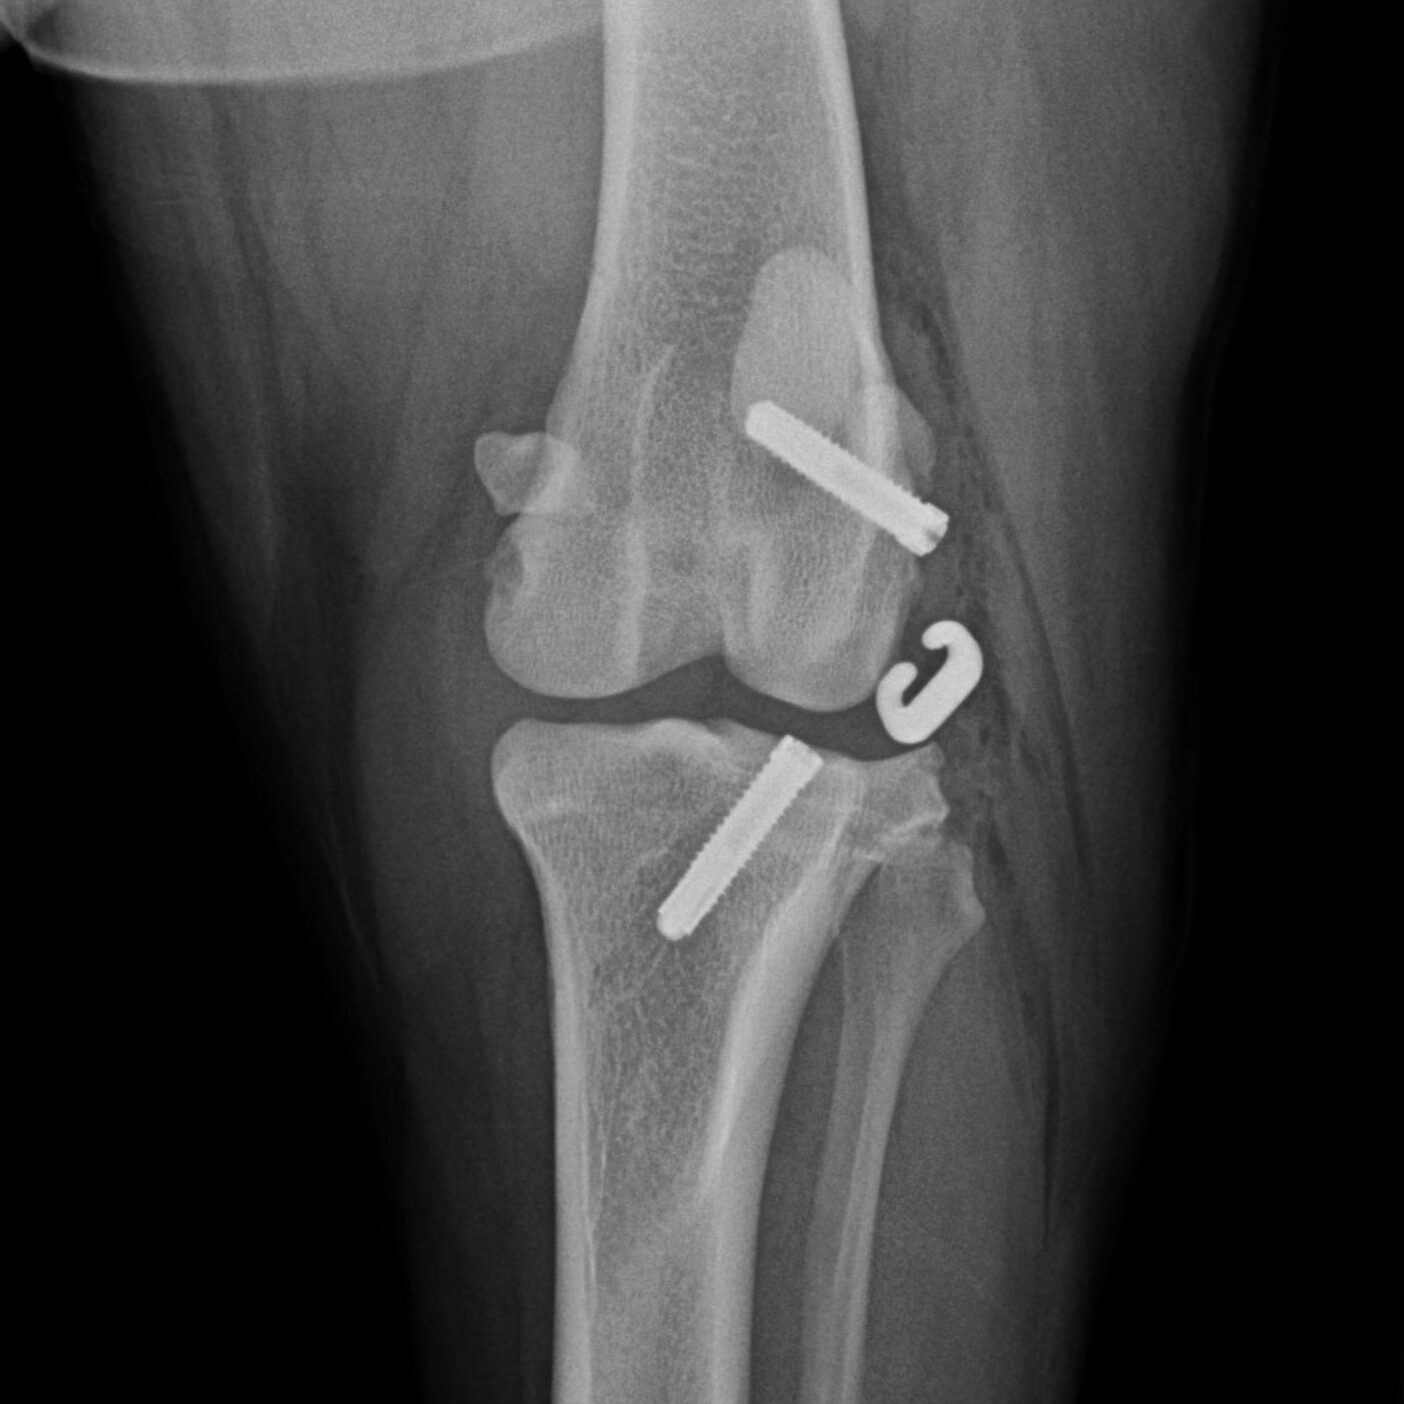

Knochenchirurgie

- Frakturversorgung, Korrekturosteotomie, u.a., verschiedenste Methoden wie Fixateur externe, interne Implantationen von Drähten, Nägeln, Schrauben, Platten inklusive SOP u.a.

Gelenkchirurgie inklusive Arthroskopie

- Kreuzbandriss, Meniskusläsionen, Patellaluxation, laxe Schulter, Isolierter Processus anconaeus, Fragmentierter Processus coronoideus, Osteochondrosis dissecans, Luxationen, Frakturen u.a.